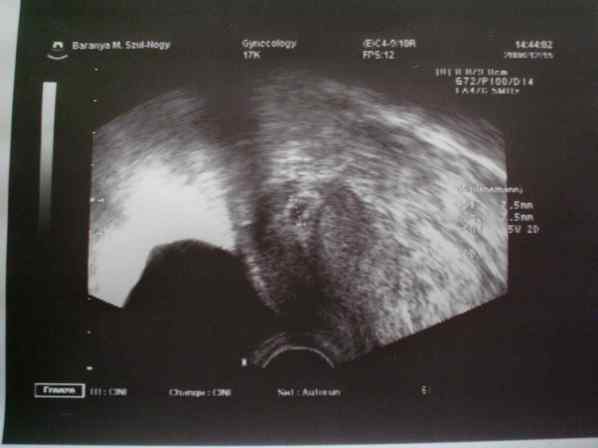

Szóval az a helyzet, hogy november 11-én jött meg a menzim utoljára, mindenféle tüneteket produkáltam, míg végül 33. cn (ez e hét szerdán volt) lett egy ilyenem:

Kép

Majd pénteken, tegnap voltam UH-n, akkor meg lett egy ilyenem:

Tegnap töltöttem az 5 hetet, és az UH szerint is anyni vagyok :) SPONTÁN!!!!!!

2 műtét és egy hormonkezelés után, hát már a lombikra készültem lelkileg :)